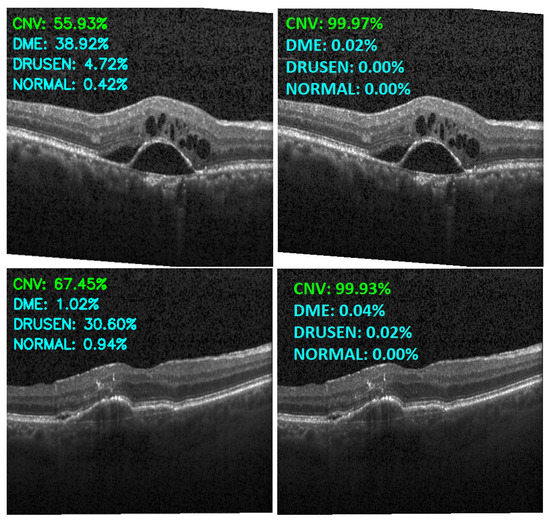

Figure 13, Figure 14, Figure 15 and Figure 16 show several examples of the proposed model performance (accuracy and classification confidence score) on OCT images using the original and augmented dataset-trained model, respectively.

Figure 13.

Exemplary result of proposed model trained without (left column) and with (right column) augmentation (correct label highlighted in green).